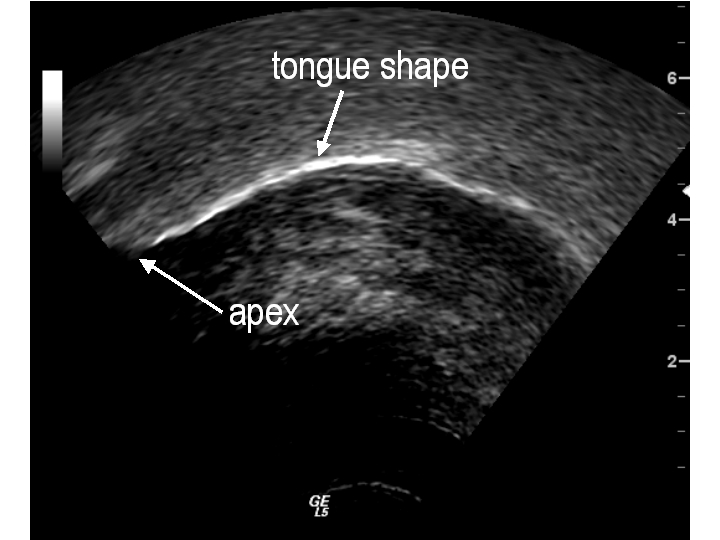

One advantage of using

ultrasound biofeedback for children with persisting speech errors is that both

the clinician and the child have more information about what the child is doing

with the tongue when he or she speaks. Additionally, clinicians can provide

more direct and explicit cues to the child, such as “move this part of your

tongue up here,” and the child can readily see if the movement was produced

properly.